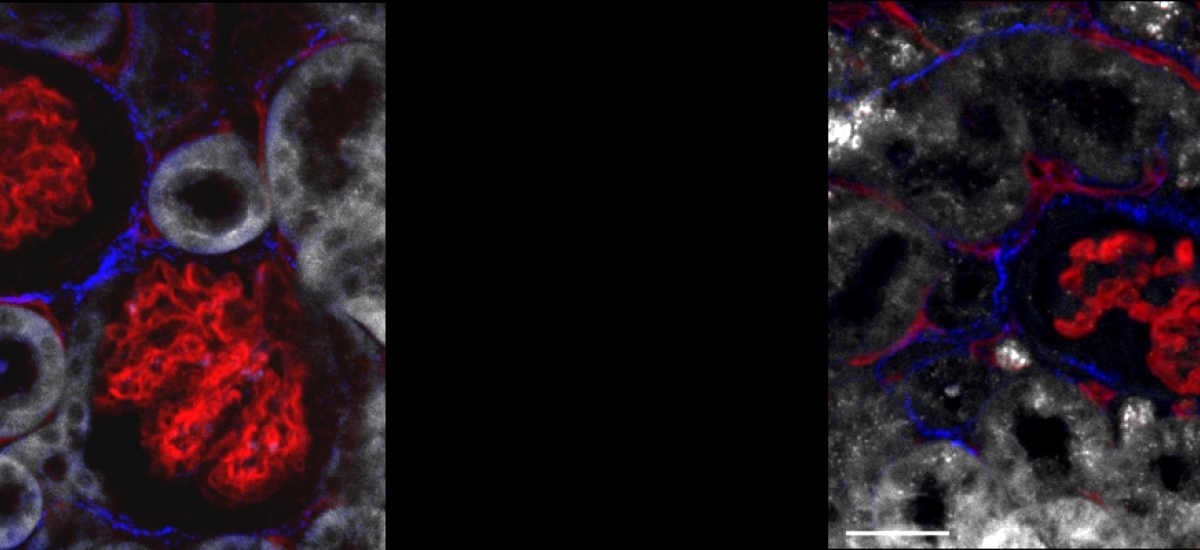

Video by Nature about our newly published paper named "A network of trans-cortical capillaries as mainstay for blood circulation in long bones" in Nature Metabolism (English only).